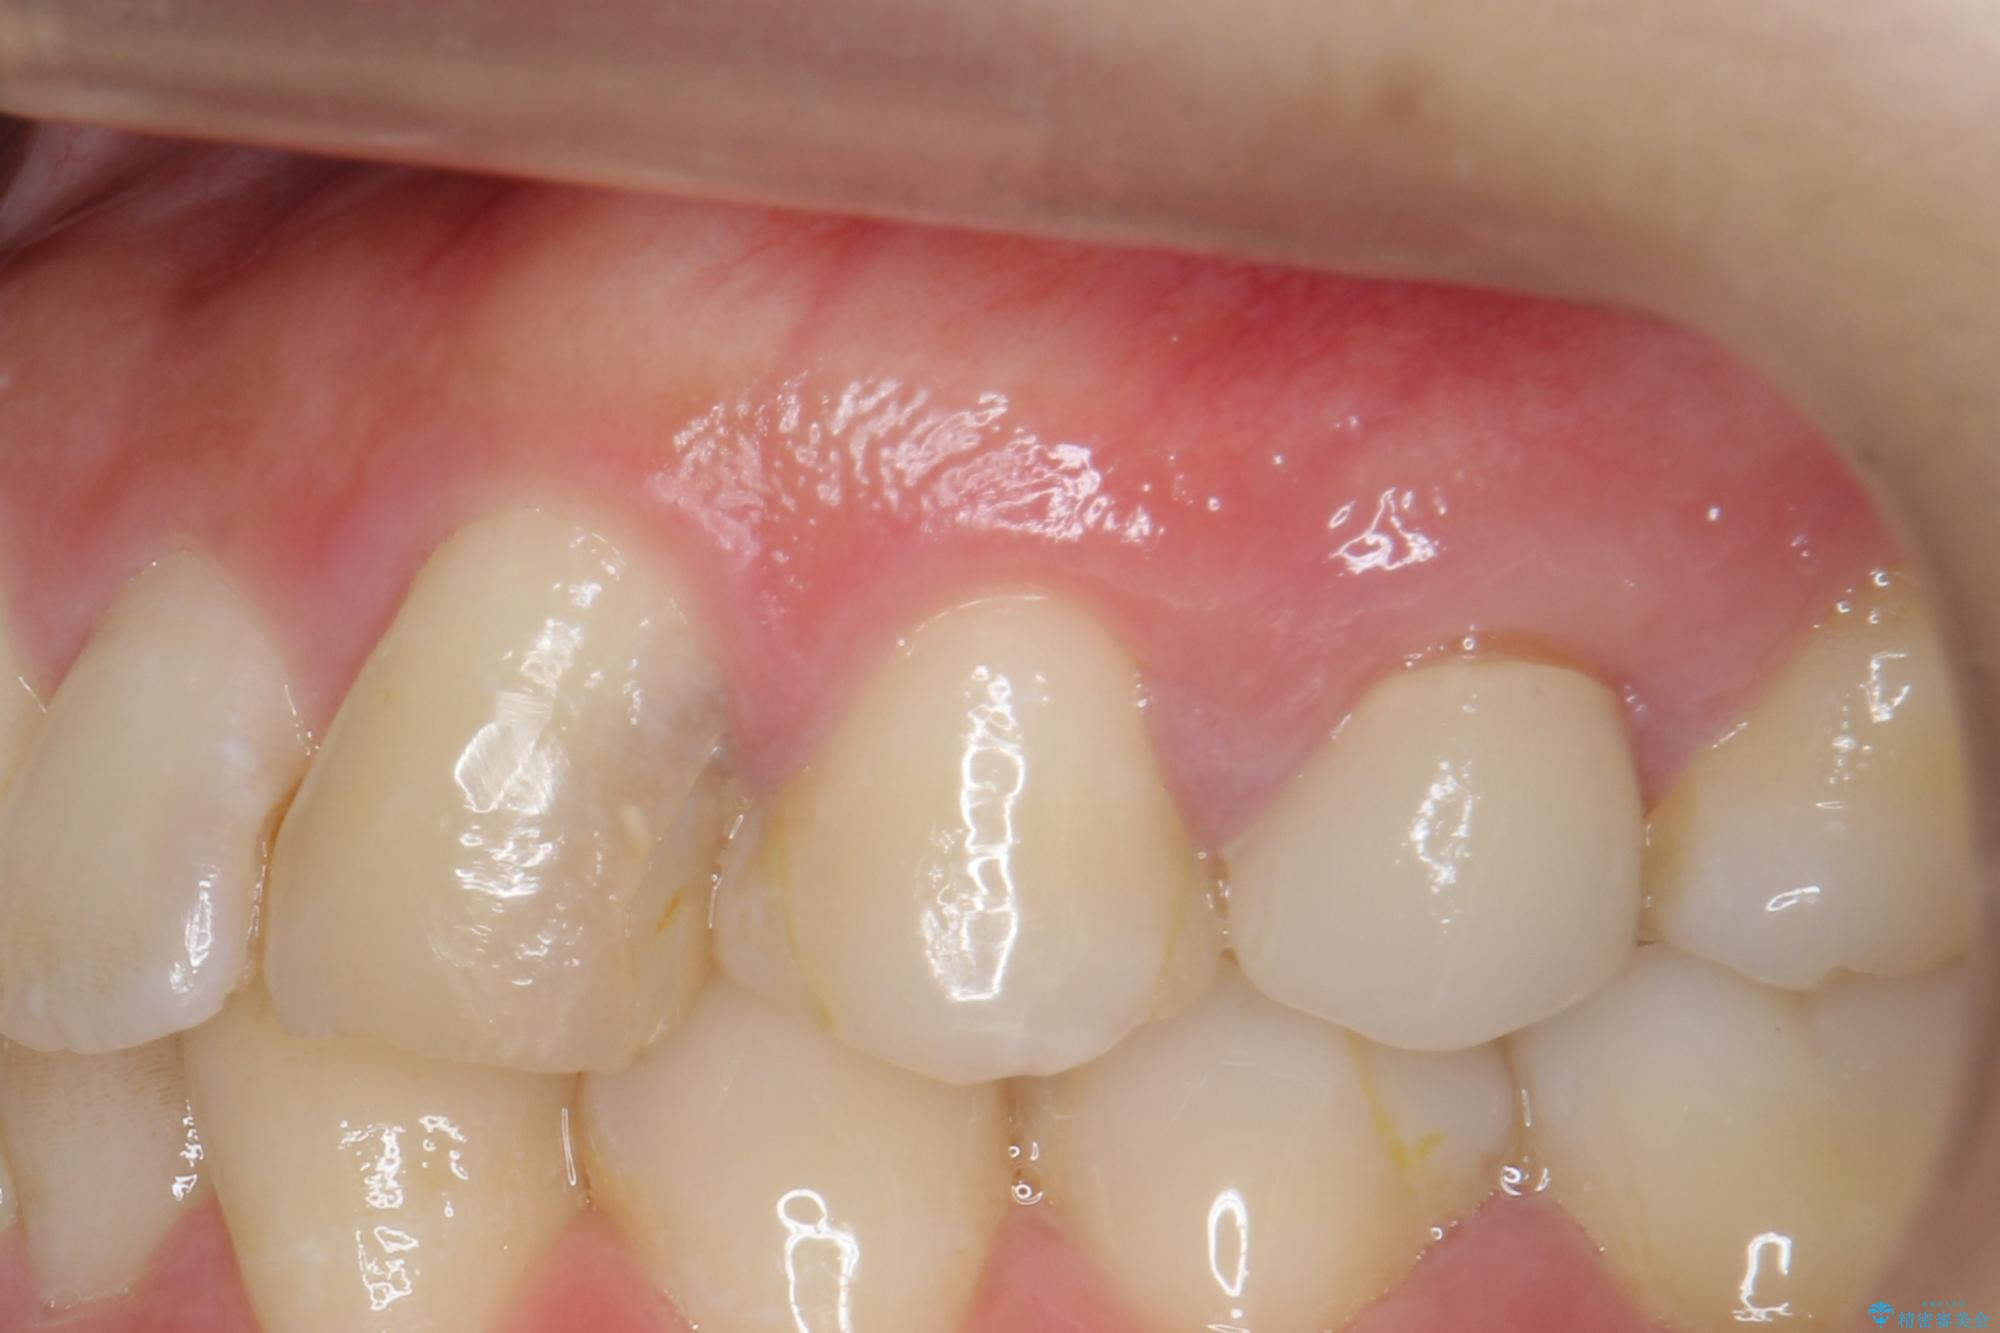

- 歯ぐきの腫れや、歯の内部が黒く見えることからの虫歯の治療を求めて来院されました。

虫歯が大きかったことから、神経の温存はできたものの歯ぐきよりも深い虫歯の問題を解決するため部分矯正治療を併用したセラミック治療を行うこととしました。

当初、歯ぐきよりも深い虫歯のぞんざいや、歯のポジションに問題がありましたがマルチブラケットを用いた部分矯正を行うことで適切な位置へと歯を移動させ、歯周環境を整えたセラミック治療を行うことができました。